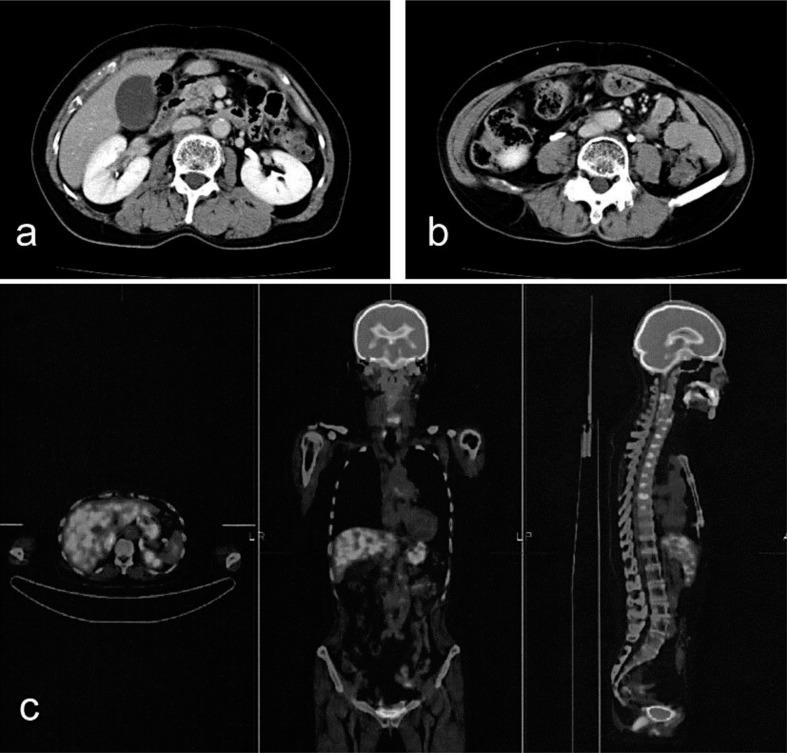

Para-aortic lymph node recurrence is a rare type of metastasis from colorectal cancer, and no treatment has yet been established. Here, we report on a case of isolated para-aortic lymph node metastasis from rectosigmoid cancer that showed complete response to chemoradiation therapy with capecitabine/oxaliplatin plus bevacizumab. A 58-year-old woman underwent high anterior resection for rectosigmoid cancer in 2009. Para-aortic lymph node recurrence occurred in 2011. She underwent radiation therapy (50 Gy) and 8 courses of capecitabine/oxaliplatin plus bevacizumab. Abdominal computed tomography and positron emission tomography with 18-fluorodeoxyglucose did not reveal any para-aortic lymph node recurrence after chemoradiation therapy. Hence, this case was interpreted as a complete response. No recurrence was noted 6 months after the complete response. Chemoradiation therapy with capecitabine/oxaliplatin plus bevacizumab is likely to be effective in treating patients with para-aortic lymph node recurrence.

主动脉旁淋巴结复发是结直肠癌一种罕见的转移类型,目前尚未确立有效的治疗方法。在此,我们报告一例乙状结肠癌孤立性主动脉旁淋巴结转移患者,该患者接受卡培他滨/奥沙利铂联合贝伐单抗的放化疗后获得完全缓解。一名58岁女性于2009年接受了乙状结肠癌根治性手术。2011年出现主动脉旁淋巴结复发。她接受了放射治疗(50 Gy)以及8个周期的卡培他滨/奥沙利铂联合贝伐单抗治疗。放化疗后,腹部计算机断层扫描及18氟脱氧葡萄糖正电子发射断层扫描均未发现主动脉旁淋巴结复发。因此,该病例被判定为完全缓解。完全缓解6个月后未发现复发。卡培他滨/奥沙利铂联合贝伐单抗的放化疗可能对治疗主动脉旁淋巴结复发患者有效。